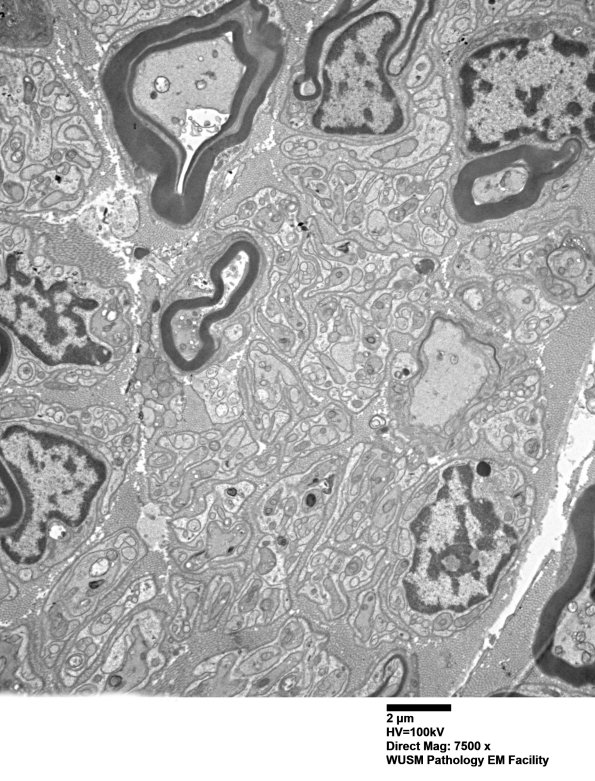

Washington University Experience | PERIPHERAL NEUROPATHY | 1 NORMAL NERVE ANATOMY | 6 Infant Peripheral Nerve | 2B4 W20-132 A (Case 2) tibial_004 - Copy

2B4,5 A second example of an axon undergoing early myelination. (electron micrograph)